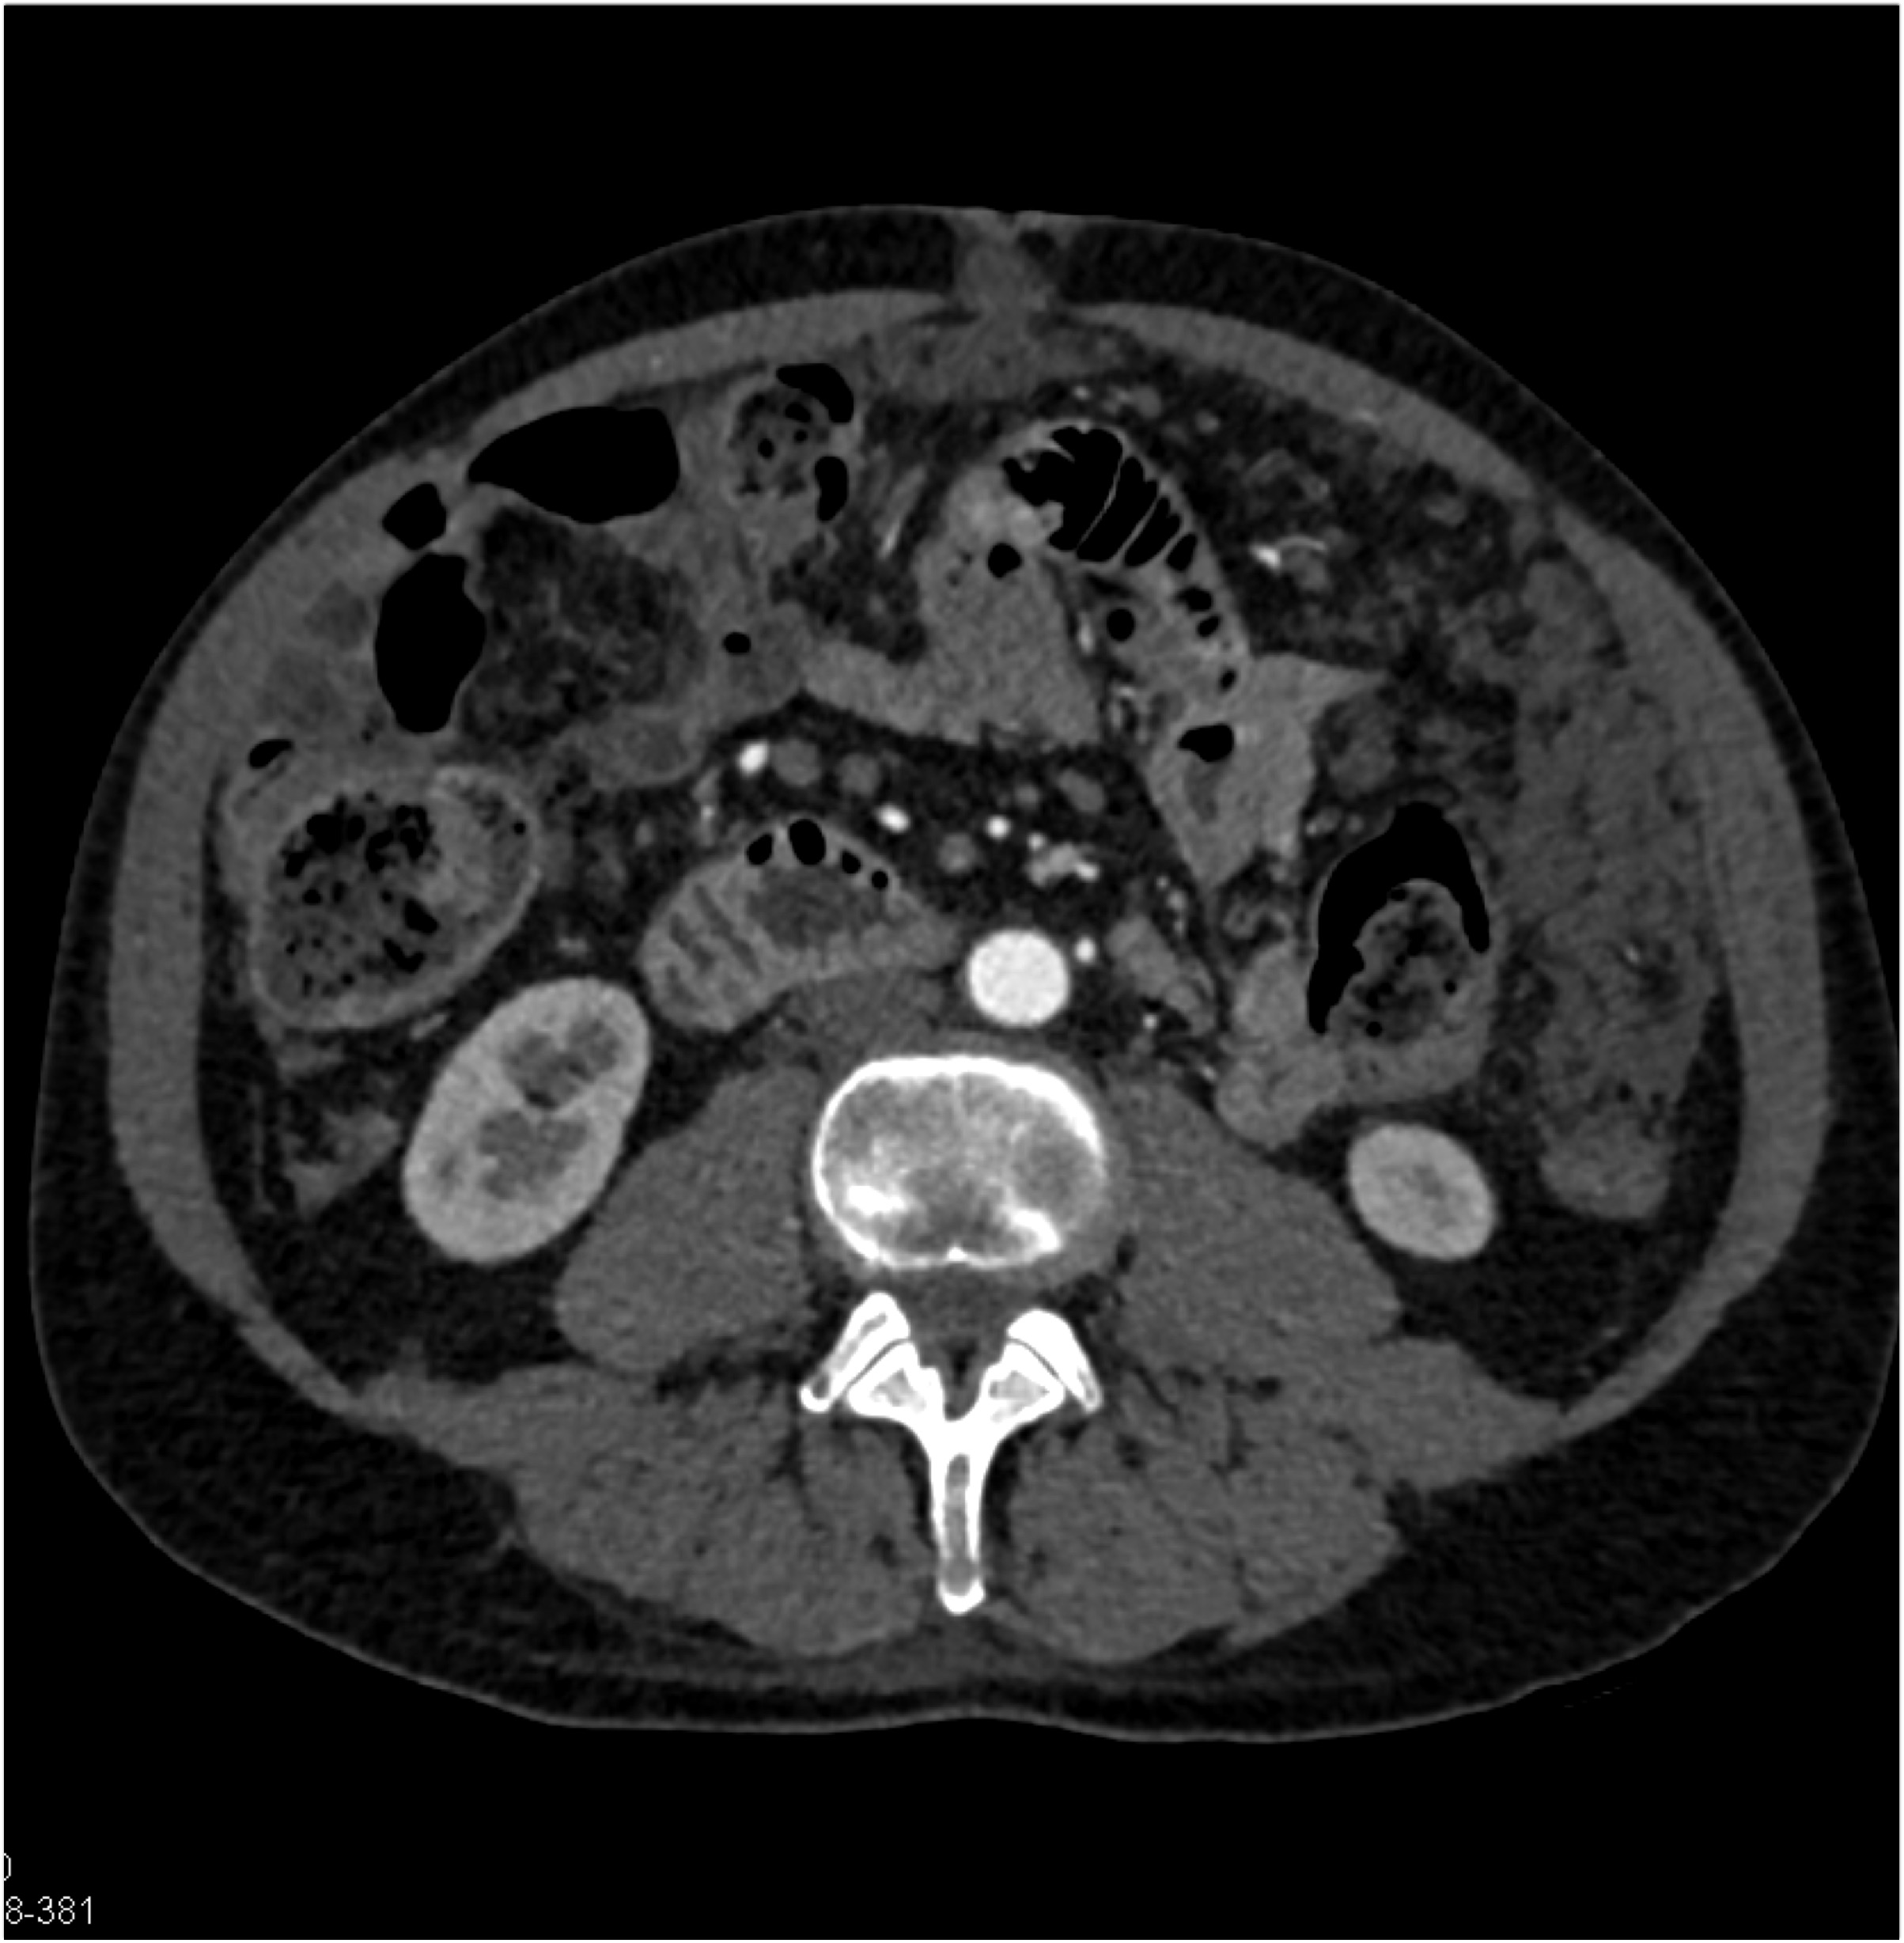

Quiz Discussion

7) The least likely diagnosis in this case is?

lymphoma

adenocarcinoma cecum

carcinoma terminal ileum

undistended normal colon

8) The least likely diagnosis in this case is

oncocytoma

papillary RCC

clear cell RCC

Bosniak 3 Cyst